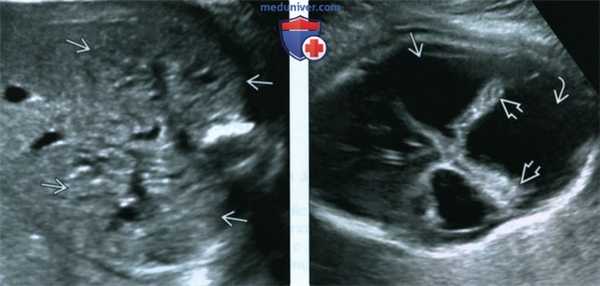

(Слева) УЗИ плода в III триместре, поперечная плоскость, косой срез. Околоплодные воды отсутствуют, определяются увеличенные гиперэхогенные почки.

(Справа) Тот же плод. УЗИ головного мозга. Определяются признаки мальформации Денди-Уокера: расхождение полушарий мозжечка, отсутствие червя, наличие крупной кисты в ЗЧЯ и вентрикуломегалия. Несмотря на то что характерной находкой для синдрома Меккеля-Грубера является затылочное энцефалоцеле, возможны и другие аномалии ЦНС.